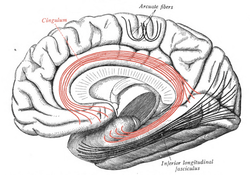

![]() Medial surface of right cerebral hemisphere. Some of major association tracts are depicted. Cingulum is at center, in red. | |

In neuroanatomy, the cingulum is a collection of white matter fibers projecting from the cingulate gyrus to the entorhinal cortex in the brain, allowing for communication between components of the limbic system. It forms the white matter core of the cingulate gyrus, following it from the subcallosal gyrus of the frontal lobe beneath the rostrum of corpus callosum to the parahippocampal gyrus and uncus of the temporal lobe.[1]

The cingulum is described from various brain images as a C shaped structure within the brain that wraps around the frontal lobe to the temporal lobe right above the corpus callosum. It is located beneath the cingulate gyrus within the medial surface of the brain therefore encircling the entire brain. There are two primary parts of the cingulate cortex: the posterior cingulate cortex and the anterior cingulate cortex. The anterior is linked to emotion, especially apathy and depression. Here function and structure changes are related meaning any change within this structure would lead to a function change, particularly behavioral because of its function involving emotions. Damage to this area can have various effects on mental disorders and mental health. The posterior section is more related to cognitive functions. This can include attention, visual and spatial skills, working memory and general memory. Because of its location, the cingulum is very important to brain structure connectivity and the integration of information that it receives.[3]